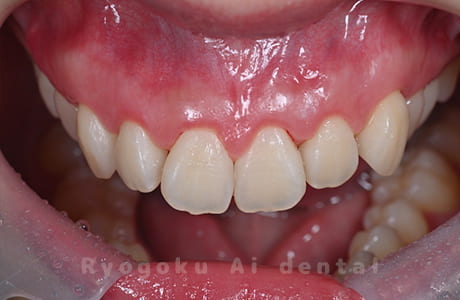

STEP 4

- 術後

- 手術後の状態の確認と記録を取ります。

笑った時に歯茎が見えてしまうガミースマイルを改善したいとのことでご来院された患者様です。術後も大変満足していただきました。